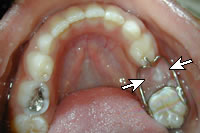

• Hàm giữ khoảng cố định: Hàm này được lưu giữ nhờ các khâu nắn chỉnh răng hoặc các chụp thép có sẵn. Hàm giữ khoảng cố định có thể ở một bên hoặc hai bên. Ưu điểm: ít vướng, đắt tiền, hiệu quả hơn vì cố định. Nhược điểm: đòi hỏi vệ sinh tốt, phải chuẩn bị răng trụ, không phục hồi lại được kích thước dọc của khớp cắn, có thể bị bong hoặc gãy. Hàm này được chỉ định trong những trường hợp: mất một răng ở một bên, mất hai bên: trong trường hợp này hàm cần có các khâu nắn chỉnh và hàm có cấu tạo giống như cung lưỡi.